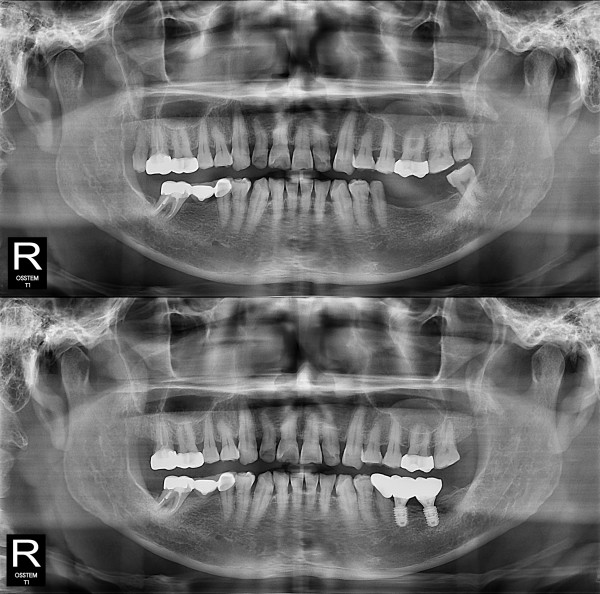

种植牙

局部种植牙